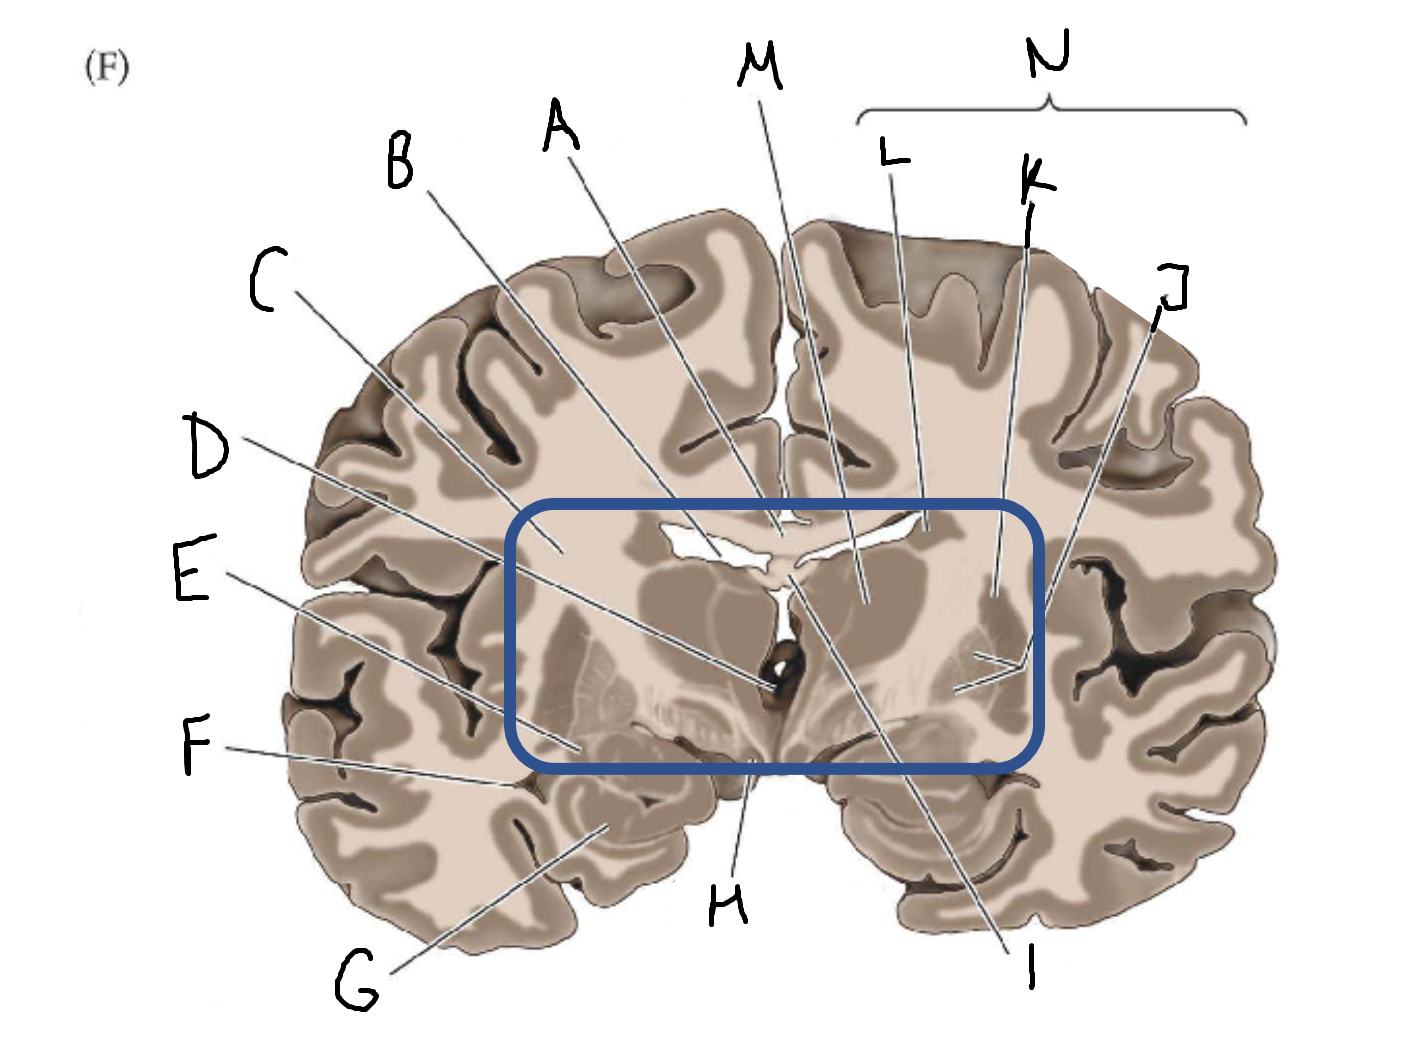

A

corpus callosum

B

lateral ventricle

C

internal capsule

D

third ventricle

E

tail of caudate nucleus

F

lateral ventricle

G

hippocampus

H

mammillary body

I

fornix

J

globus pallidus

K

putamen

L

caudate

M

thalamus

N

basal ganglia